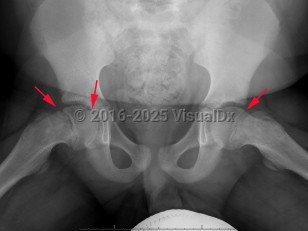

Slipped capital femoral epiphysis

Classic history and presentation: This condition most commonly presents with groin, thigh, hip, and/or knee pain. The pain can be chronic or acute and can be constant or occur only when weight-bearing. Pain is more often unilateral but can occur bilaterally.

Pathophysiology: SCFE occurs due to mechanical forces acting on the growth plate as there is a weakness in the hypertrophic zone. In adolescents, there are increased shearing forces as the growth plate is still vertical and the perichondrial ring is thin and weakened. These increased shearing forces result in the femoral head shifting off the femoral neck through the growth plate.

Another classification tool is the Southwick slip angle classification. This uses the epiphyseal-diaphyseal angle, which can be measured on both anteroposterior (AP) and frog-leg lateral pelvis imaging. SCFE can be classified as mild if the angle is less than 30 degrees, moderate if between 30 and 50 degrees, and severe if greater than 50 degrees.